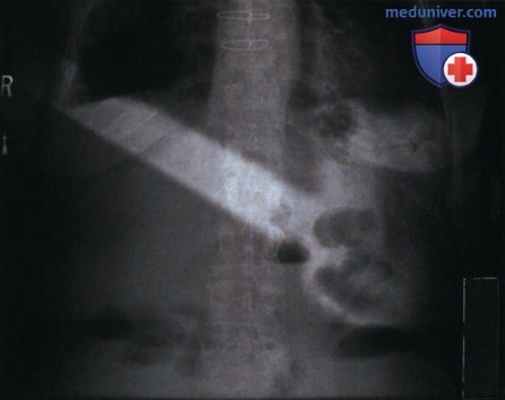

РИСУНОК 1 Рентгенограмма органов брюшной полости в ПЗ проекции, полученная в положении пациента лежа на спине с положенной на живот кистью. Вероятно, это вина не рентгенолога, а пациента, который положил руку на живот для удобства, когда врач покинул диагностический кабинет. Этот пример показывает необходимость объяснения пациенту порядка проведения исследования и то, как важно сохранять правильное положение, заданное рентгенологом. Кроме того, если между укладкой пациента и экспозицией прошло много времени, необходимо снова убедиться в правильности положения пациента. Нередко пациенты, испытывающие боли в тазобедренном суставе или пояснице, подкладывают под них кисть, что приводит к ее наложению на зону интереса. РИСУНОК 2 Рентгенограмма органов грудной клетки в ПЗ проекции, полученная на передвижном аппарате. Руки пациента были расположены близко к туловищу. Поскольку изучение плечевых костей не является целью исследования, то и включать их в экспозиционное поле не следует.

• Представляют собой любую анатомическую структуру в пределах экспозиционного поля, которую нельзя убрать. Если такая структура не накладывается на область ЗИ, то ее можно исключить при обработке (рис. 1 и 2)